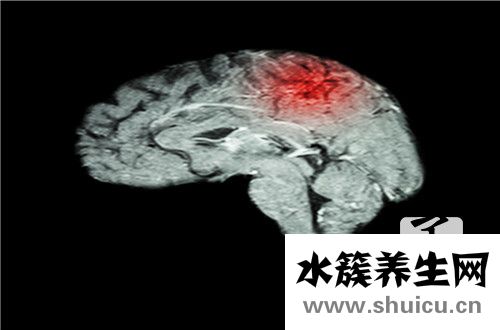

腦出血的出現將嚴重威脅患者的身心健康,甚至威脅生命立即。 腦出血的跡象是什么? 這是許多朋友想知道的,希望能夠合理地預防腦出血。 在患有腦出血的患者中,指甲上出現鮮紅色或灰黑色暗點,這些斑點都很明顯較為。

腦溢血的征兆

在病人的指甲上,如果有鮮紅色乃至灰黑色的黑斑出現,就代表著身體血液循環出現了阻礙,這就是腦溢血前兆。